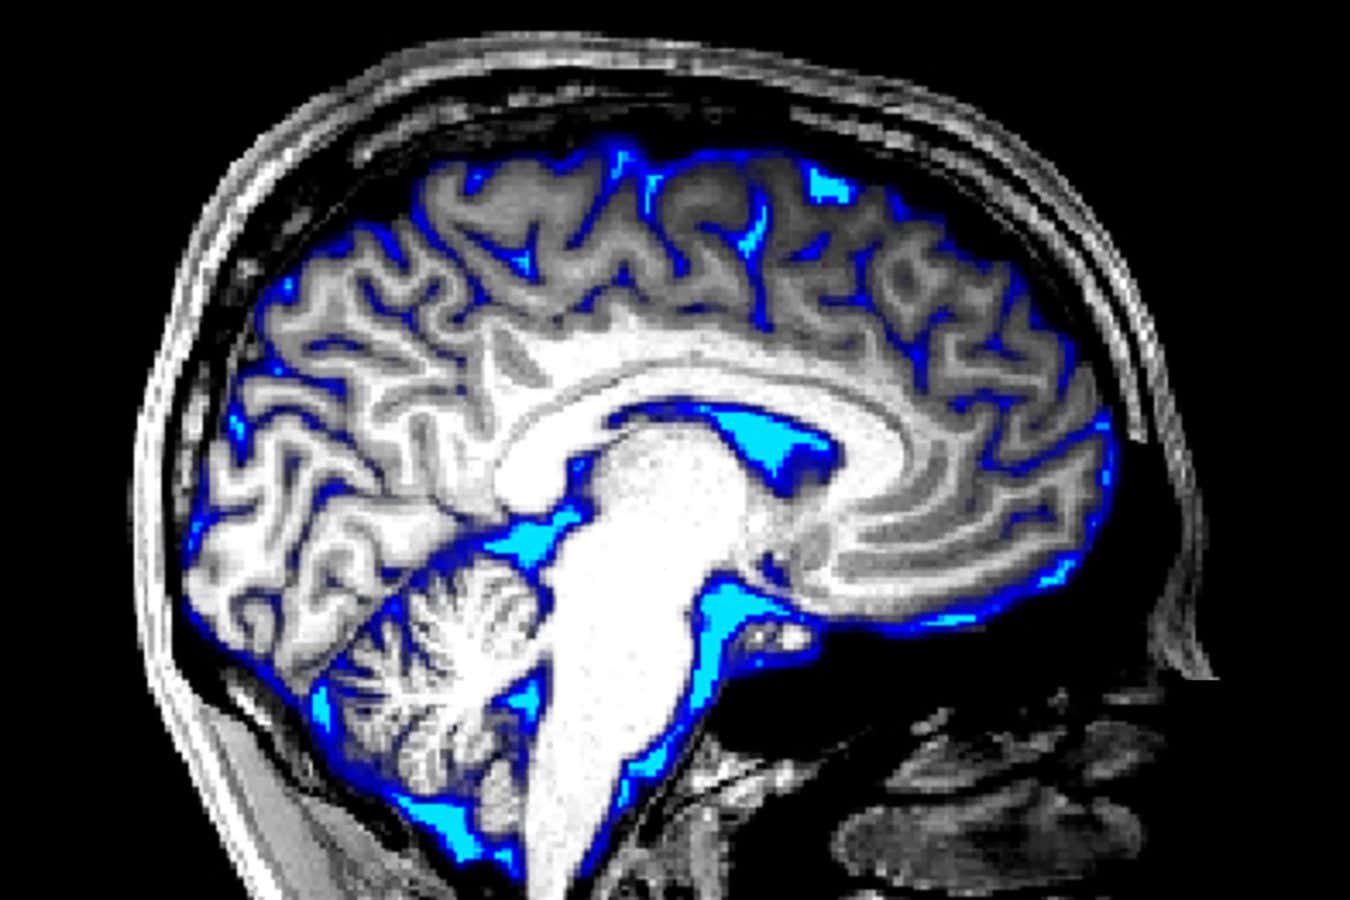

The glymphatic platform is comprised of channels that clear waste from the brainCLAUS LUNAU/SCIENCE PHOTO LIBRARY

The glymphatic platform is comprised of channels that clear waste from the brain

Our brain removes metabolic waste via the glymphatic platform, a network of channels surrounding the blood vessels that pump waste fluid to the lymphatic platform, where it is carried to the blood for disposal.

The glymphatic platform is most active during deeper phases of sleep, when slow brain waves help push along waste fluid after it has been released from brain cells. But it becomes impaired with age, and especially during Alzheimer’s disease.